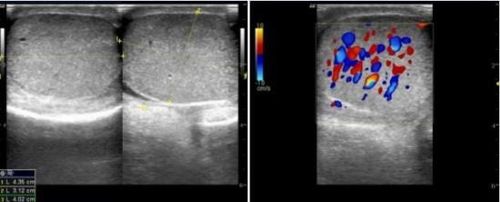

Thông qua quy trình siêu âm tinh hoàn sẽ phát hiện những hình ảnh bất thường như các đám rối thừng tinh xoắn thành từng búi do tắc nghẽn khiến máu bị ứ lại, không lưu thông, đồng thời đánh giá dòng chảy của máu bên trong búi giãn tĩnh mạch thừng tinh.

Xoắn tinh hoàn là bệnh lý cấp tính nguy hiểm, nếu không phát hiện kịp thời có thể gây hoại tử tinh hoàn. Bệnh hay gặp ở nam giới từ 10 - 25 tuổi. Siêu âm tinh hoàn doppler có khả năng phát hiện xoắn tinh hoàn cũng như đánh giá mức độ xoắn để xử trí kịp thời, tránh biến chứng xảy ra.

Hình ảnh viêm tình hoàn bên trái trên siêu âm